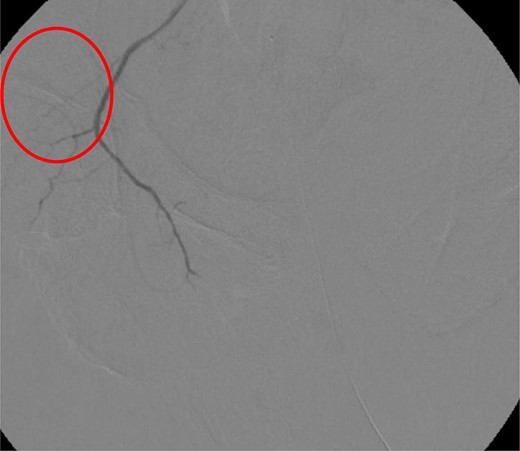

CT abdomen/pelvis with contrast was performed and a blush of contrast was noted posterior to the right pubic bone. Prior to taking patient for exploratory surgery, he was transferred to the interventional radiology suite where a pelvic angiogram was performed revealing an abnormal blush localized to the distal branches of the right iliolumbar artery (Fig. 2). Delayed phase of the angiogram demonstrated early venous filling consistent with a traumatic arteriovenous fistula which was embolized with 300–500 µ of embospheres and three 3 × 2 microcoils (Figs 3 and 4).

CT angiogram delayed phase of angiogram shows early venous filling consistent with AV fistula.